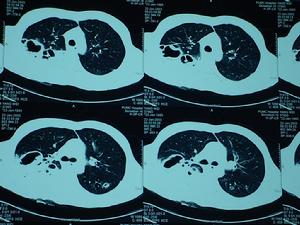

由於繼發性肺炎高發年齡段一般在5歲以內的幼兒和50歲以上的中老年人群中,因此建議5歲以內的幼兒和65歲以上的老年人接種肺炎疫苗。罹患呼吸系統疾病、心血管疾病或糖尿病的慢性病患者,一旦患上甲流更易感染肺炎並導

右肺炎症及膿腔致嚴重併發症,將大大增加住院率和病死率。因此在今年流感大規模襲擊前,這部分高危人群要引起特別注意,並提早進行免疫預防。